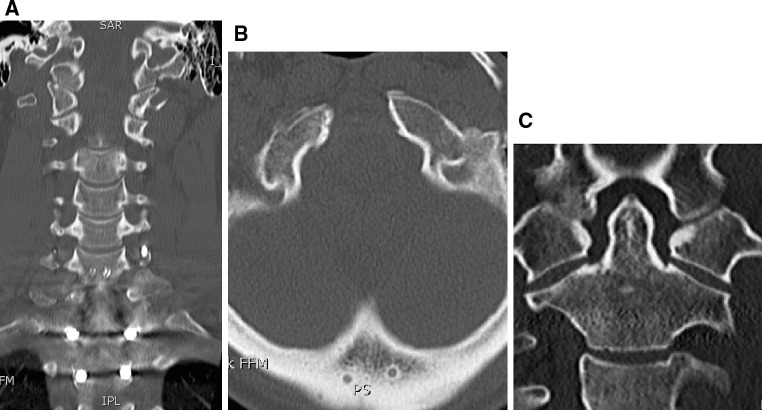

Plain radiographs of the cervical spine (antero-posterior and lateral) as well as a CT scan were performed and revealed a rotational burst fracture of C7 with partial occlusion of the right C7 foramen (Fig. 1). The fracture was classified as C3.1 according to Magerl and Reinhold [1, 2]. Furthermore, a slightly displaced occipital condyle fracture on the right side could be detected (Fig. 2). This fracture was classified as a type III according to Anderson and Montesano [3], and type 2A according to Tuli [4], respectively. In the axial view, a rotational misalignment of 22° to the left of C0/1 against C2 could be observed (Fig. 3).

Fig. 3.

Left rotatory subluxation (CO/1–C2) of 22° due to bony avulsion fracture